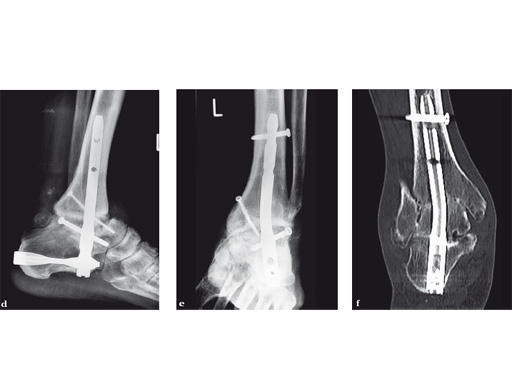

A 64-year-old man presented with severe ankle and subtalar arthritis accompanied by large cysts in the talus and calcaneus. Eighteen months after hindfoot fusion with the HAN he walked without pain.

Case provided by Stefan Rammelt, Dresden, Germany